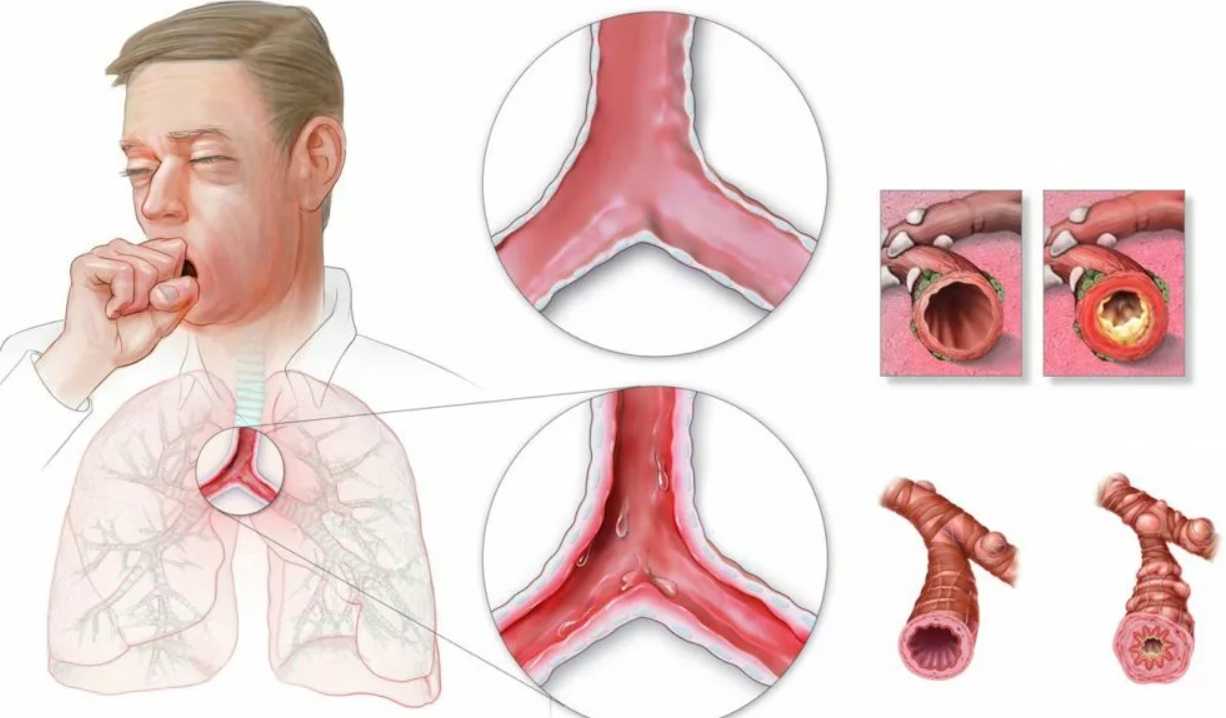

Обычно бронхит имеет ярко выраженную симптоматику, которая облегчает постановку диагноза. К типичным признакам болезни относятся:

- дискомфорт в области грудной клетки:

- температура и озноб;

- одышка;

- слабость и чувство усталости;

- отделение мокроты (зеленого, желтовато-серого, прозрачного цвета, в редких случаях с прожилками крови);

- кашель (сухой или влажный).

Бронхит без температуры у взрослого может иметь следующие симптомы:

- длительный кашель;

- хорошо прослушивающиеся хрипы и свисты;